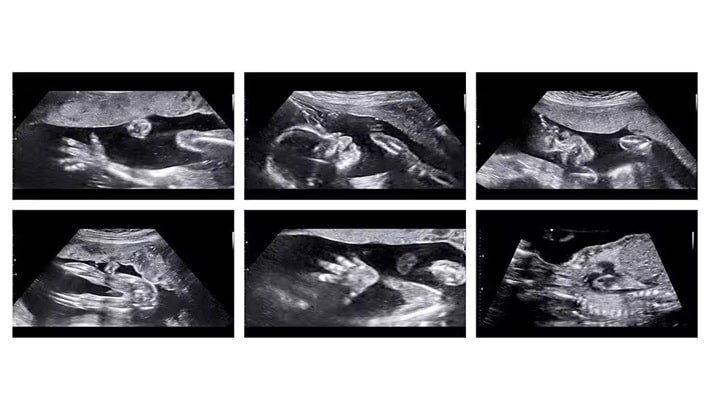

سونوگرافی آنومالی یکی از اصلیترین مراحل بررسی سلامت جنین در دوران بارداری است. این سونوگرافی معمولاً بین هفتههای ۱۸ تا ۲۲ بارداری انجام میشود و هدف آن بررسی جزئیترین قسمتهای بدن جنین است. پزشک با کمک تصاویر دقیق، رشد اندامها و وجود احتمالی ناهنجاریهای مادرزادی را کنترل میکند.

سونوگرافی آنومالی چه چیزهایی را بررسی میکند؟

این نوع سونوگرافی تقریباً همه اندامهای اصلی جنین را بهطور کامل ارزیابی میکند. پزشک بهدنبال اطمینان از رشد طبیعی اندامها و نبود مشکلات ساختاری است.

بررسی مغز و ستون فقرات

با کمک سونوگرافی آنومالی میتوان ساختار مغز و ستون فقرات را بررسی کرد. ناهنجاریهای جدی یا مشکلات مغزی در این مرحله قابل شناسایی هستند.

بررسی قلب و عروق

قلب جنین یکی از اندامهای حیاتی است که باید بهطور دقیق بررسی شود. پزشک با دقت شکل و عملکرد قلب را بررسی میکند تا مشکلات احتمالی قلبی-عروقی تشخیص داده شود.

بررسی اندامهای شکمی و لگنی

اندامهایی مانند معده، کلیهها، مثانه و کبد نیز با دقت بررسی میشوند. وجود یا عدم وجود مایعات در اندامها میتواند اطلاعات مهمی در اختیار پزشک قرار دهد.

بررسی اندامهای حرکتی جنین

دستها، پاها و انگشتان جنین در سونوگرافی آنومالی بهوضوح دیده میشوند. این بخش برای والدین بسیار هیجانانگیز است، زیرا اولین بار است که حرکات کوچک جنین را میبینند.